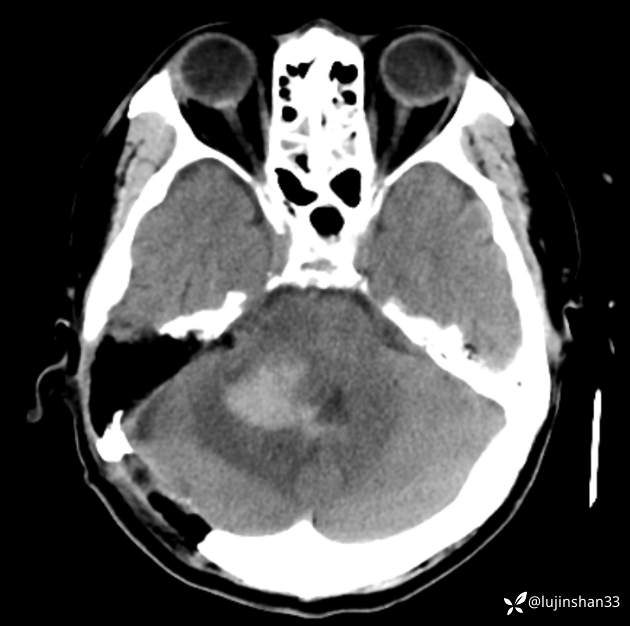

术前CT及MRI

临床诊断:右侧桥小脑角血管母细胞瘤

讨论:桥小脑角区占位,血供情况如何判定?良恶性如何从影像学判定?